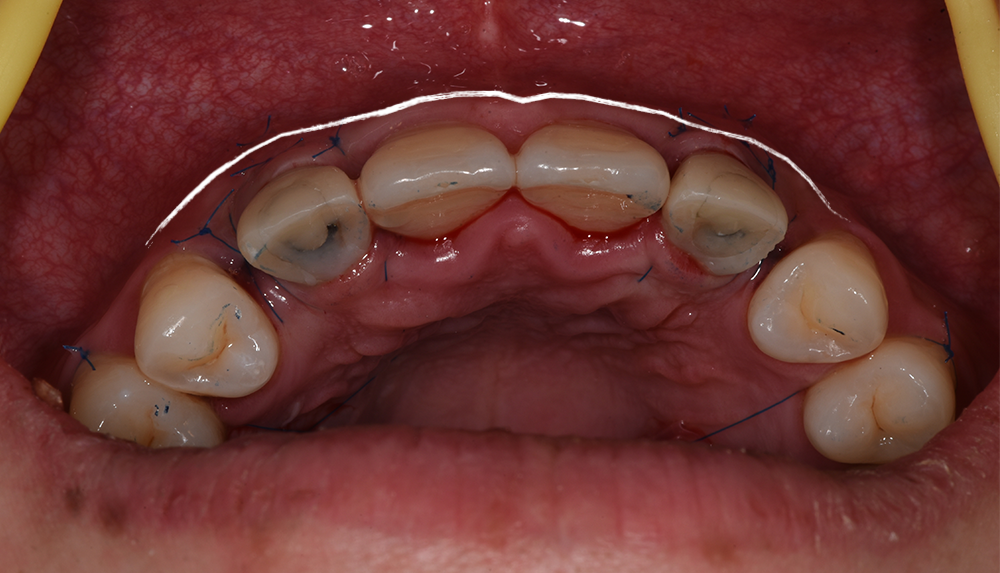

颌面观显示12、22区轮廓丰满度良好

临时修复体邻接良好

12、22牙正中及前伸运动无咬合接触

术后10天拆线,龈乳头处软组织较术后有所改善

术后10天拆线,唇侧褥式缝合保留未拆,拆线后取模制作保持器